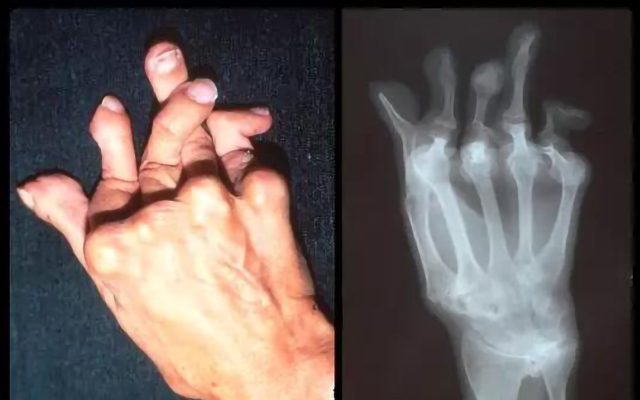

風(fēng)濕病是因為機(jī)體免疫功能紊亂而導(dǎo)致的全身性疾病,可損及關(guān)節(jié)、肌肉、內(nèi)臟等多個靶器官,關(guān)節(jié)是常見也是受累多的部位,由于多樣復(fù)雜的發(fā)病因素和受治療技術(shù)、治療條件的限制,大多數(shù)患者因為沒有條件接受系統(tǒng)、規(guī)范的治療,病情得不到有效控制而終導(dǎo)致身體殘疾。據(jù)國家衛(wèi)健委統(tǒng)計,目前我國風(fēng)濕病患者數(shù)量約為2.5億人,重癥患者有8000萬人,其中約有53%的患者因疾病導(dǎo)致肢體殘疾,因此風(fēng)濕病被醫(yī)學(xué)界稱之為“頭號致殘疾病”。

圖:類風(fēng)濕導(dǎo)致手指殘疾